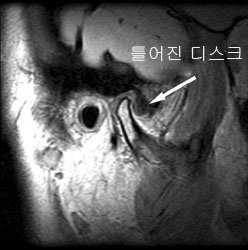

하악돌기, 측두골의 관절면, 관절 캡슐, 관절 디스크, 인대, 외익상근 등으로 구성된다.